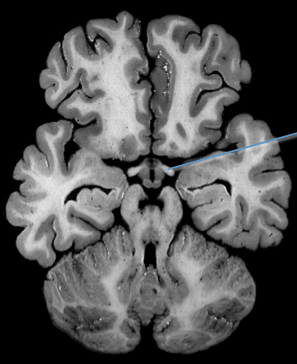

optic tract

thalamus and the crus cerebri

A lesion of the right optic tract causes a complete loss of vision in the left hemifield:

contralateral “homonymous” hemianopsia.

(can see crus cerebri but not optic tracts yet)